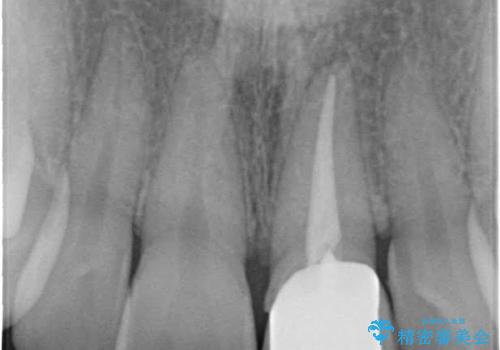

今回は、仮歯の状態で歯の長さを調整する歯周外科をおこなう

→歯茎の治りを待っている間、根管治療のやり直しを行う

→土台を築造しセラミックを完成させる

ことで前歯を残し、長さが揃うようにしました。

左上の前歯がわずかに短いことを気にされていたため、歯周外科にてこれを可及的に改善し、セラミックにて修復を行いました。